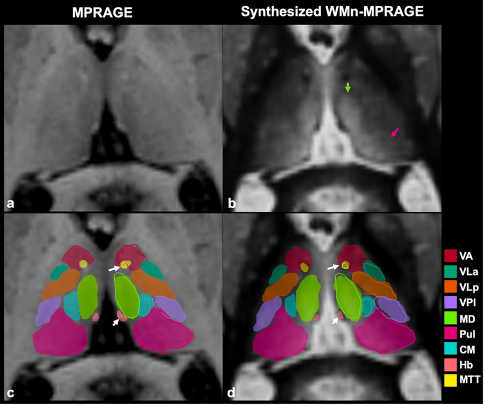

THalamus Optimized Multi Atlas Segmentation (THOMAS) is a state of the art method we have developed for segmentation of WMn MRI data. It uses 20 prior manually segmented data sets for segmentation of new input data. We have also adapted THOMAS to segment the more readily available T1 MRI data, albeit with some reduction in accuracy. THOMAS has also been modified to create an atlas in MNI space which has been incorporated into leaddbs, a very popular open source software for DBS lead placement in neurosurgery.

More recently, we have been exploring sophisticated deep-learning methods to improve accuracy and speed of thalamic nuclear segmentation. One method synthesizes WMn MRI data from standard T1 MRI data and segments it using convolutional neural networks (CNN), opening the door for rapid analysis of databases such as ADNI, OASIS, and HCP. We have also developed a simpler more robust version using polynomial synthesis.